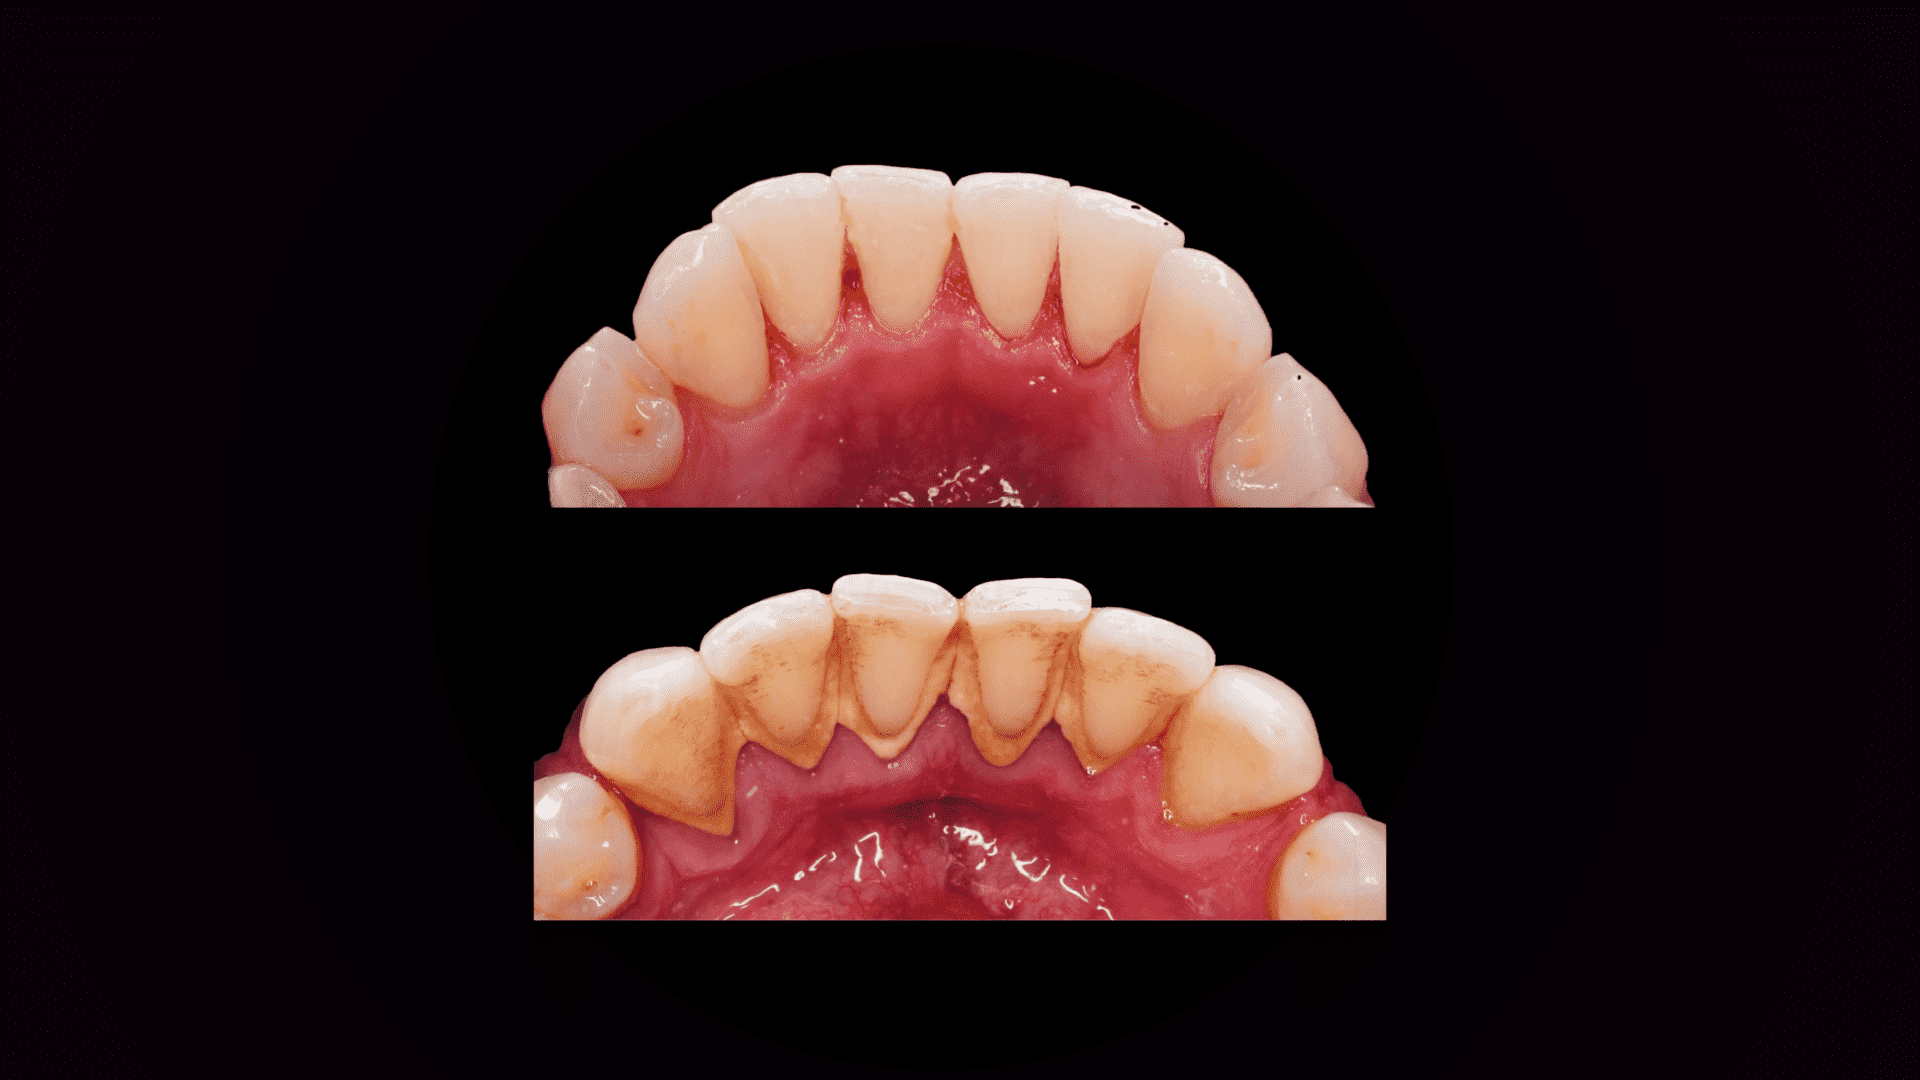

Obraz przed i po usunięciu kamienia nazębnego - wynik higienizacji

Kamień powstaje również w wyniku niedoczyszczenia. Pacjenci mówią: „przecież myję zęby”, „szczotkuję zęby 3 razy dziennie, po każdym posiłku”. Jednakże, często w pośpiechu, czasami niewłaściwą techniką, gdzie jedynie masujemy zęby na przykład kolistym ruchem (ponieważ tak nas uczyli w szkole). Niestety, w ten sposób nie ma możliwości właściwego oczyszczenia strefy nad i pod dziąsłowej, czy przestrzeni międzyzębowych. Nieusunięta płytka ulega zwapnieniu i mamy kamień. Możemy go zauważyć jako zażółcenie lub zbrązowienie na zębie, tuż przy dziąśle. Ale najbardziej groźny jest kamień, którego nie widać, ten umiejscowiony pod dziąsłem. Takie typowe objawy mogące świadczyć o jego istnieniu to: krwawiące dziąsła, zaczerwienione dziąsła, wrażliwość i obrzęk, czasami nieprzyjemny zapach z ust.